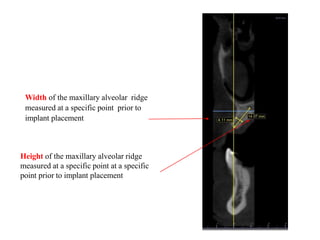

Width of the maxillary alveolar ridge

measured at a specific point prior to

implant placement

Height of the maxillary alveolar ridge

measured at a specific point at a specific

point prior to implant placement